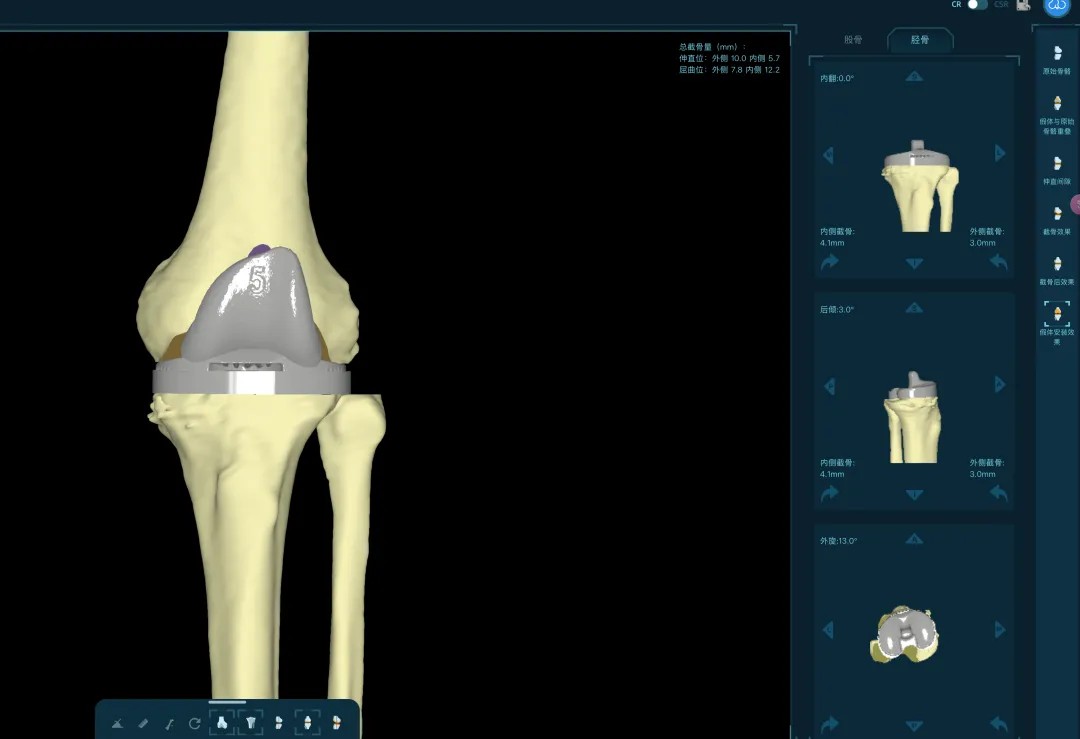

通过患者的CT数据,系统构建出膝关节的三维数字模型,精确评估骨缺损的范围与形态。医生可以在虚拟空间中,提前模拟手术过程,为患者“量体裁衣”,规划出假体安放的最佳位置、角度以及所需填充骨缺损的特殊垫块型号。

“这相当于在真实战斗前,进行了一次全方位的沙盘推演。”罗军介绍,这种规划确保了手术的精准度,缩短了手术时间,也为使用先进的翻修假体系统做好了完美铺垫。

本次手术的核心,是采用了Evolution® ECCK膝关节翻修系统。该系统专为应对翻修手术中常见的严重骨缺损、韧带功能不全等极端复杂情况而设计。

其模块化的组件提供了前所未有的灵活性,就像一套高精度的“工程套件”,允许医生在术中根据实际骨缺损情况,自由组合不同尺寸的垫块、延长杆等部件,实现关节线和力学稳定性的个体化重建。